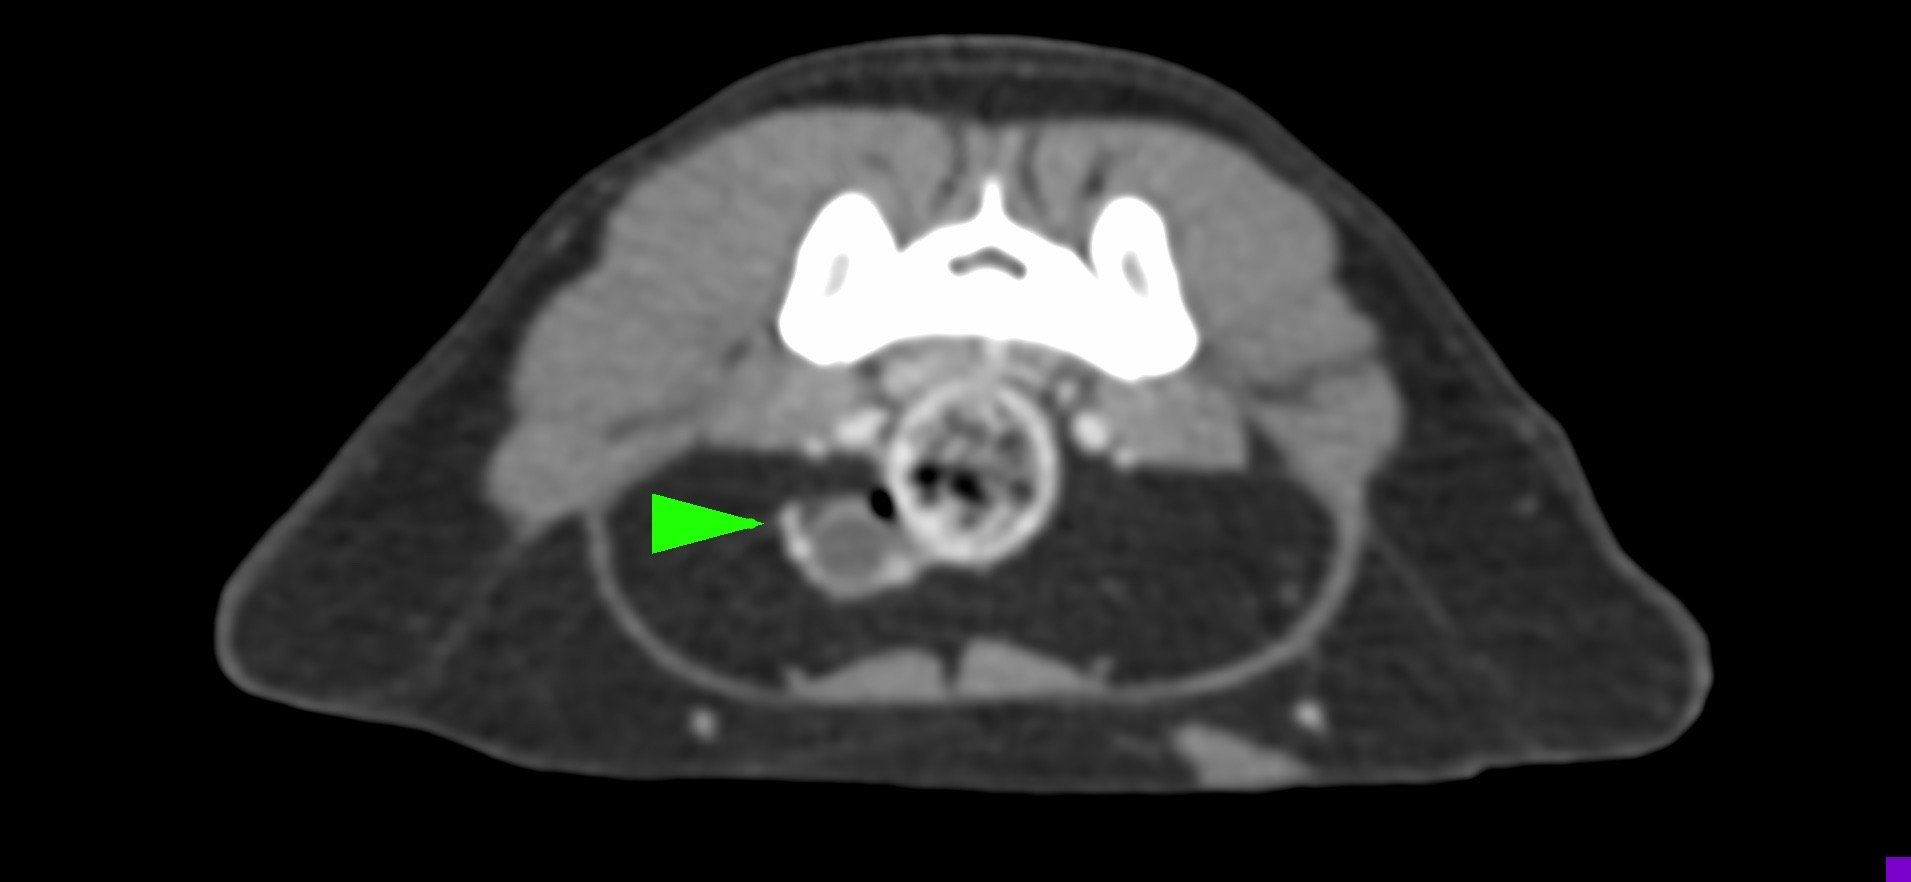

狗狗後腳癱瘓也有可能是血栓 不一定是骨骼神經肌肉問題喔

後肢癱瘓的柴柴經由他院轉診來築心做電腦斷層掃瞄因為狗狗以前病史有椎間盤突出問題

所以以為是脊椎問題想要來評估手術

掃瞄結果診斷為動脈血栓造成

主動脈血栓栓塞是一種急性且危及生命的疾病,當血液凝塊從心臟或其他部位脫落,經過血液循環流向並卡住動脈中的某些血管,造成局部的血液供應中斷、相應部位的器官或組織缺氧,將引起疼痛、損傷甚至壞死。

此患犬在電腦斷層影像以及後續追蹤的超音波下都可見明顯血栓影像